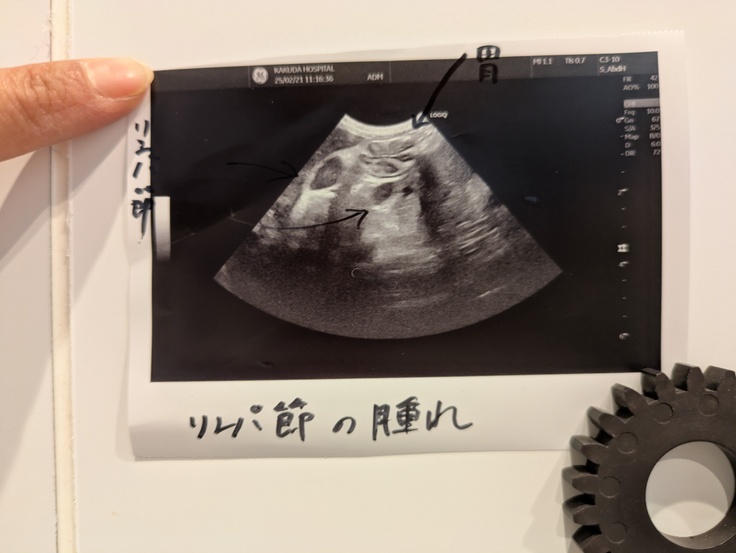

私は喉や腸になにかがあるんじゃないかと疑っていましたがエコーの結果リンパ節が腫れていることが分かりました。

飲み薬は吐いてしまうので抗生剤の注射となりました。

また、血液検査では炎症は口腔内にあることが分かりやはり抜歯とかスケーリングだね。というお話になりました。